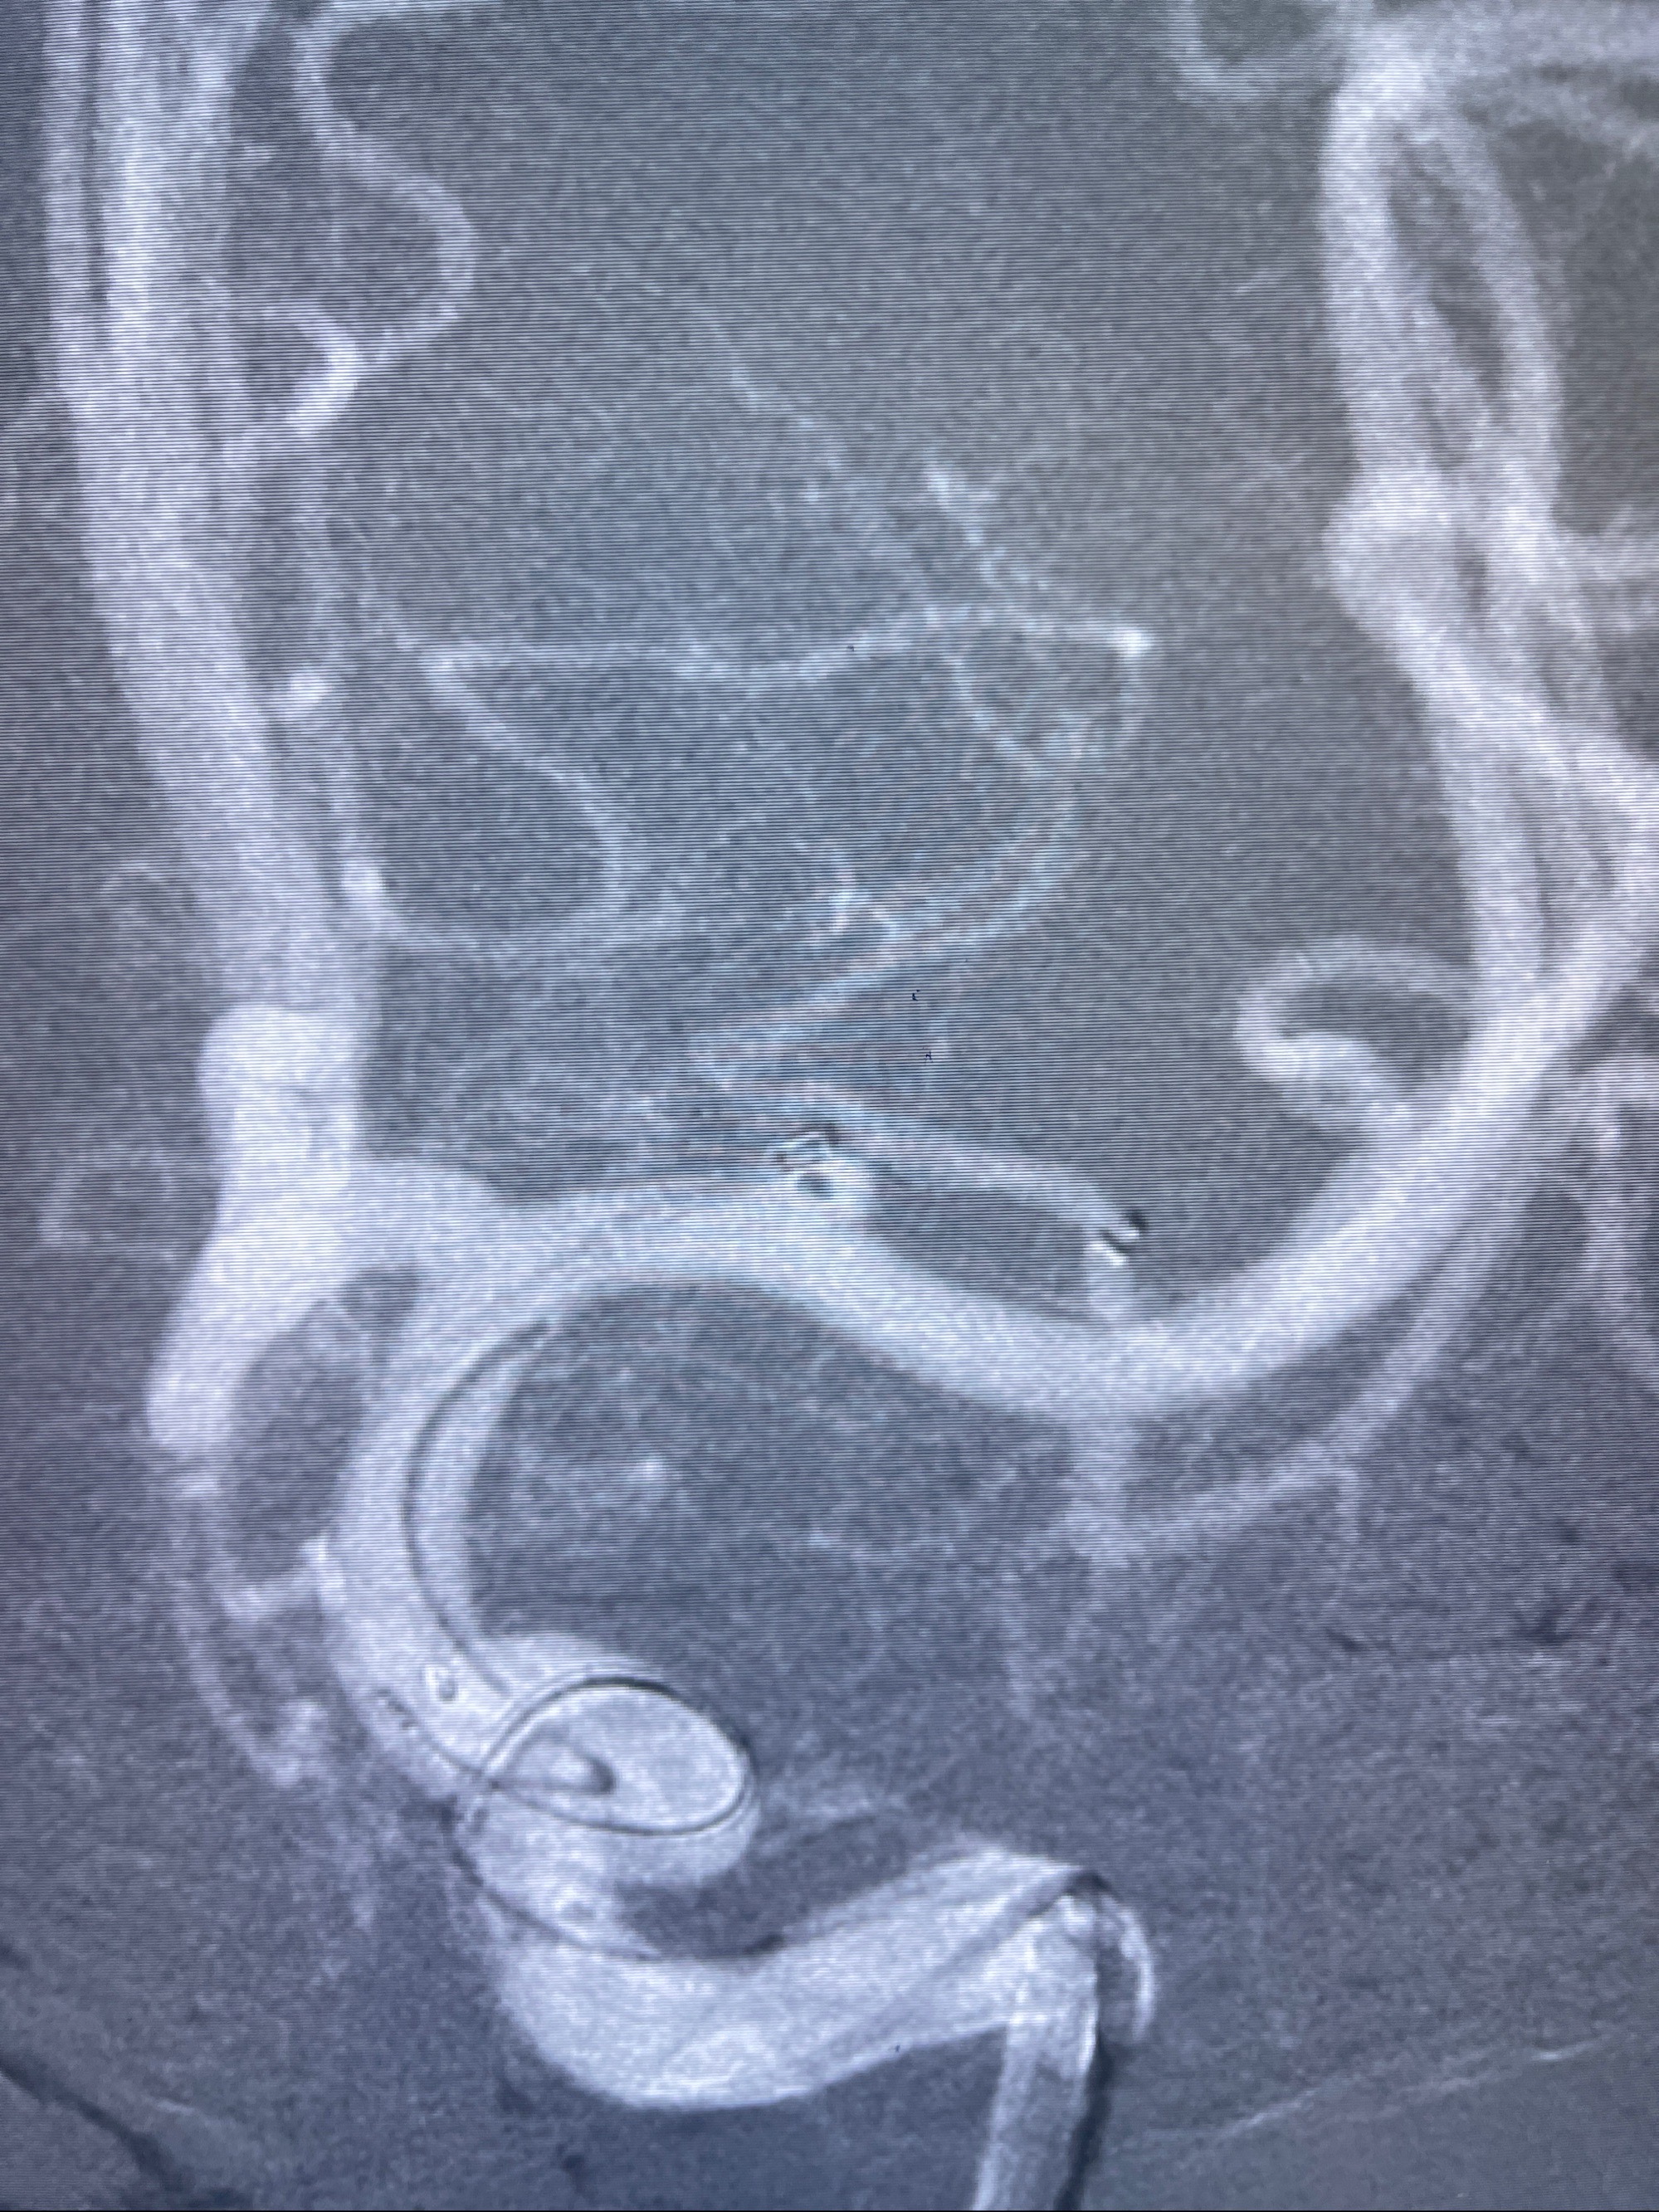

2.外科手术夹闭or介入支架辅助栓塞

麻醉苏醒佳,遵嘱动作

术后即刻CT